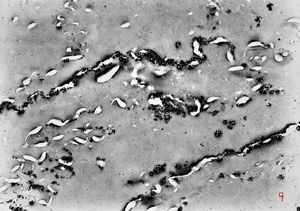

clotted blood - fibrin and granulocytes

F,44y. | striations of fibrin - heart atrium, myxoma

M,28y. | striations of fibrin - aortal valve, endocarditis